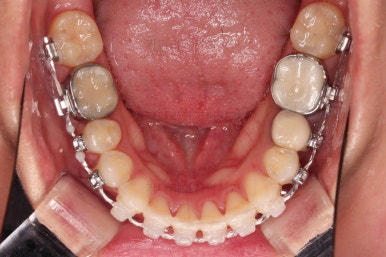

마찬가지로 초진 시 입안의 모습입니다.

입안 사진을 보니 문제점이 보이죠.

바로 어금니가 없는 상태였습니다.

물론 치열도 그리 많이 삐뚠 편은 아니고, 치아가 없으니 심플하게 임플란트를 해 넣으면 되지 않겠나 라고 생각할 수 있지만요.

나이도 많이 어리시고, 임플란트를 한다는 심리적 저항감도 있었고요.

한 번 임플란트를 해 넣으면 교정치료가 매우 힘들어진다는 점과 겸사겸사 돌출감도 개선하고자 하는 의지가 있으셔서 임플란트 없이 사랑니를 살려서 어금니 대신 쓰는 부산사랑니교정 치료를 해보기로 했습니다.